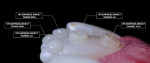

At the next appointment, the area was isolated (OptraGate®, Ivoclar Vivadent), and the composite mock-up was easily removed because tooth No. 9 was nonvital and did not require anesthesia. Shade buttons (IPS Empress® Direct Flow [A3.5], [A3], [A2], [Trans Opal], Ivoclar Vivadent) were placed on tooth No. 8 according to the strategic shade map to validate both the shade and the thickness needed for each material (Figure 8).3,8,11 These were then removed, tooth No. 9 was prepared with a 2.0-mm sickle-bevel at the fracture line, and a 0.5-mm chamfer margin was placed gingivally with an interproximal elbow. It should be noted that the preparation style employed was less conservative than is typical of composite resin veneers because of the nature of the discoloration. After a 1.0-mm infinite bevel was prepared onto the lingual surface and all internal and external line angles were softened using a blue disc, the lingual endodontic access was reopened, the cotton pellet was removed, and the pulp chamber was irrigated with a 2% chlorhexidine antibacterial solution (Consepsis®, Ultradent) to remove any debris and achieve disinfection. Next, a 1.0-mm circumferential bevel was placed around the access to increase bond strength, and a 37% phosphoric acid was placed on the peripheral enamel for 60 seconds, rinsed thoroughly, and dried. Two layers of bonding agent (Adhese® Universal, Ivoclar Vivadent) were then applied, vacuum thinned, and light cured for 20 seconds. To restore the 6.0-mm access (Figure 9), a thin layer of flowable composite (Tetric Evoflow® [A3.5], Ivoclar Vivadent) was placed, followed by two 3.0-mm increments of bulk-fill composite (Tetric Evoflow Bulk Fill [A3.5 Dentin], Ivoclar Vivadent), each of which was light cured for 20 seconds.8,9

The palatal index was fitted and scored along the lingual aspect of the infinite bevel using a thin gold instrument (IPCT Composite Instrument, Cosmedent). Tooth No. 9 was then etched for 60 seconds, rinsed, and dried. The bonding agent was applied in two thin coats and vacuum thinned both times prior to a 20-second light cure. Next, an increment of translucent opal composite was placed inside the index, shaped, thinned, and pressed against the lingual aspect of tooth No. 9. Using instrumentation and a brush (Compo-Brush, Smile Line), the palatal shell was formed, and then it was light cured for 20 seconds. The index was removed, and the flowable composite was applied between the palatal shell and lingual aspect of tooth No. 9 to anchor the shell. The entire restoration was then light cured for 20 seconds. Care was taken to remove any excess composite prior to curing, but after curing, the remnant flash was removed from the palatal shell using a blue disc (Figure 10).10,12